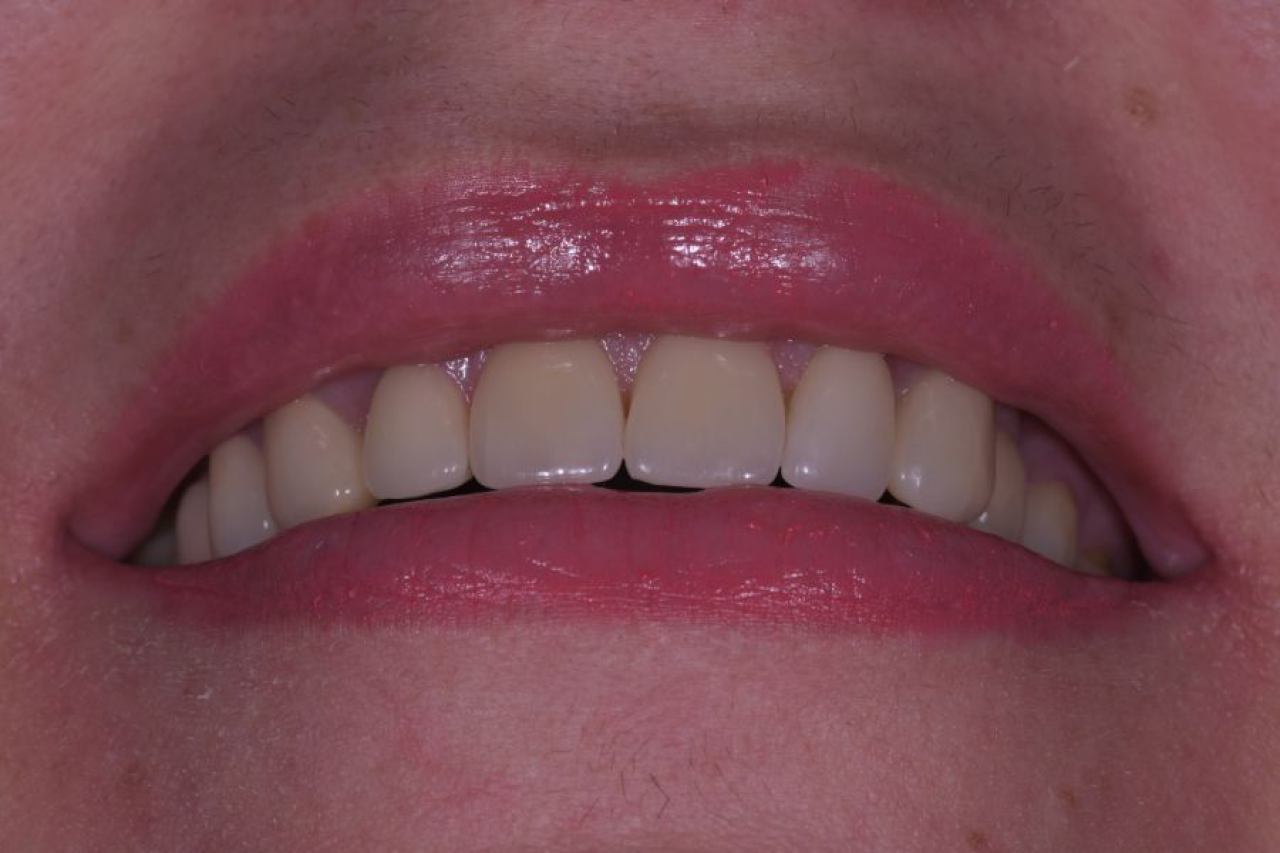

Estetska dentalna medicina

Izbjeljivanje zubi i zubne ljuskice zaštitni su znak Hollywoodskog osmijeha. Izbjeljivanje nije štetno za zube i ne oštećuje caklinu.

Ukoliko niste zadovoljni svojim osmijehom tu je DSD ili Digital Smile Design kojim u okvirima naših mogućnosti ispunjavamo vaše želje „Hollywood smile" ljuskicama, minimalno invanzivnim preparacijama zuba.

Marković Dental Clinic uvijek na prvom mjestu ima zdravlje zubi i zadovoljstvo svakog pacijenta. Koristimo najmoderniji software gdje je pacijentu moguće virtualno prikazati nove zube te kasnije kreirati novi osmijeh protetskim radom, ljuskicama, krunicama ili mostovima.